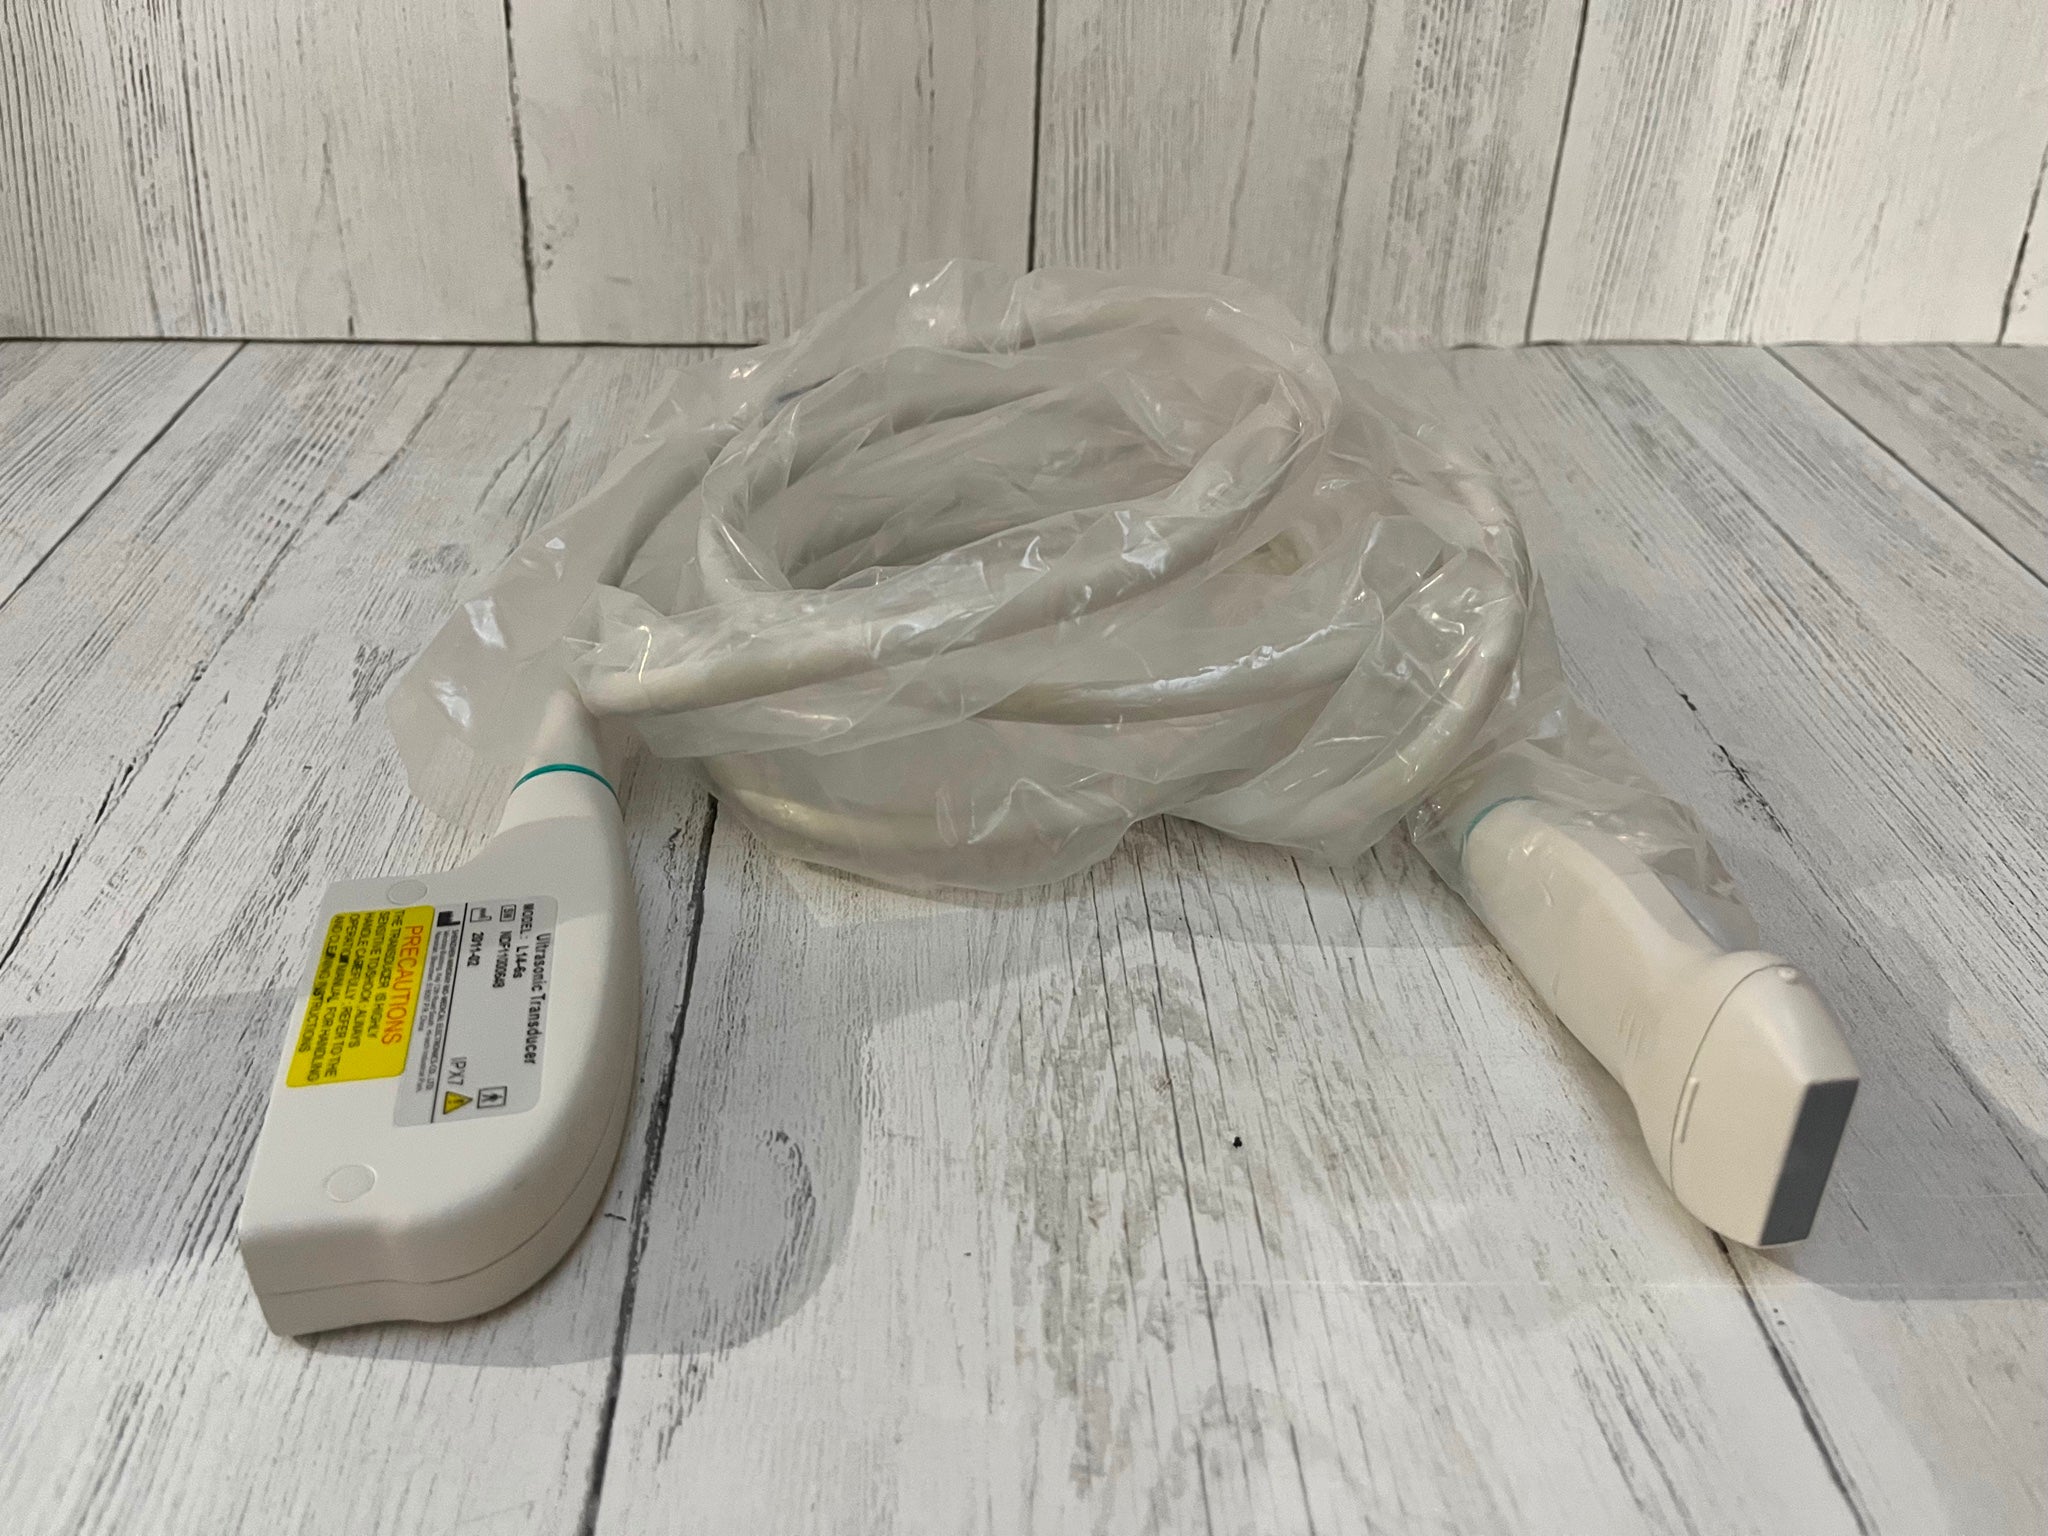

The Acuson Cypress Cardiac Vascular Ultrasound Machine is engineered for exceptional imaging and diagnostic accuracy. Its advanced technology allows for detailed visualization of cardiac and vascular structures, which is essential for healthcare providers. The inclusion of the 3V2c and 7L3 probes enhances its versatility, making it suitable for various clinical applications. As a result, this machine is a crucial tool in modern cardiology and vascular assessment.